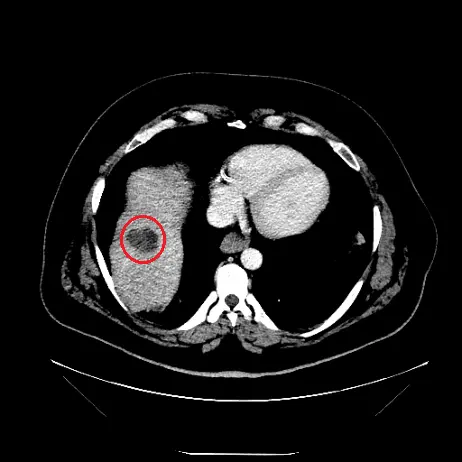

Post-op

Entraîner des algorithmes pour la prédiction de la zone d'ablation micro-onde dans le traitement du cancer sur des données cliniques réelles

Objectif : Comparer les prédictions des zones d'ablation aux zones d'ablation réelles telles que visible à l'imagerie.

✅ Mise à disposition d'une base de données structurée

✅ Sélection des patients correspondants